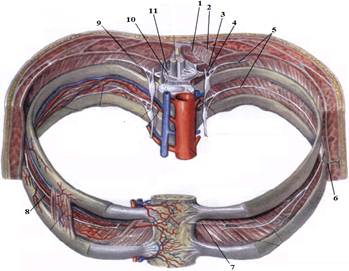

ТЕМА: Грудні нерви, розподіл дорсальних (задніх) гілок. Яремний, підключичний і бронхосередостінний стовбури. Міжреброві нерви, хід, топографія, ділянки іннервації. Судинно-нервовий пучок міжребрового проміжку.

е) склад та топографію судинно-нервового пучка міжребрового проміжку.

7. Судинно-нервовий пучок міжреберного проміжку.

На таблицях і трупах студенти знаходять судинно-нервового пучка міжребрового проміжку. Далі на трупі розглядають хід і розподіл грудних нервів та ділянки їх інервації, Користуючись таблицями вивчають лімфатичні судини і вузли грудної клітки. На трупі ззаду і справа від грудної аорти знаходять грудну протоку. Визначають її корені хід топографію. На таблицях вивчають корені правої лімфатичної протоки визначають ділянки відпливу до двох головних лімфатичних проток.Викладач консультує студентів по темі заняття, показує незрозумілі деталі будови. В кінці заняття викладач шляхом тестування кінцевого рівня знань та вмінь оцінює роботу кожного студента в академічному журналі.

1. Яким номером позначено N. thoracicus?

2. Яким номером позначено N. intercostalis?

3. Яким номером позначено R. cutaneus lateralis?

4. Яким номером позначено R. dorsalis n. thoracici?

5. Яким номером позначено R. cutaneus lateralis r.dorsalis n. thoracici?

6. Яким номером позначено R. cutaneus medialis r.dorsalis n. thoracici?

7. Яким номером позначено R. cutaneus anterior?

8. Яким номером позначено Rr.communicantes n. thoracici?

9. Яким номером позначено Radix dorsalis n. thoracici?

10. Яким номером позначено Radix ventralis n. thoracici?